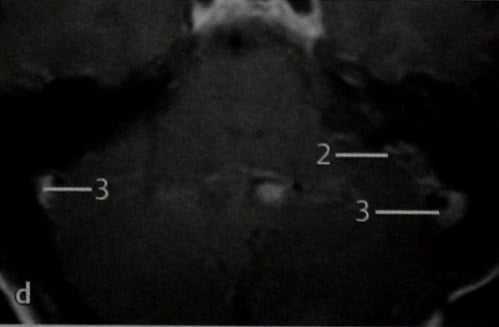

d МРТ: Т1 -взвешенное изображение в горизонтальной проекции после введения препарата гадолиния. Видно значительное усиление сигнала от опухоли, располагающейся слева (2), что подтверждают ее гиперваскуляр-ность, а также нормальный кровоток в обоих сигмовидных синусах (3).